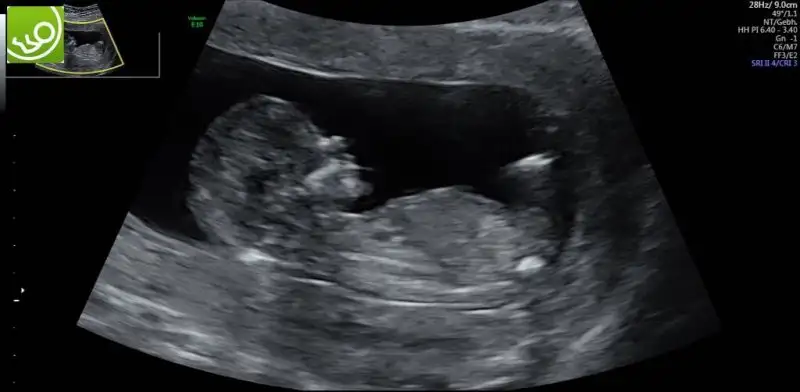

kizlar iki gunden beri icimi kemiren bisi var sizlerle paylasmak istiyorum yardimci olursaniz sevinirim ikili test yaptirdik bildiginiz uzere dr hersey normal dedi ve kan testi icin hafta ya gun verdi test kagidinda birtek mide cebi gorulmemistir yaziyordu dr haftaya gelince tekrar bakariz dedi hersey normal dedu ama benim icim icimi yiyor ne olur dua edin ve yardimci olun boyle bisi duyan varsa bilgi paylasabilir mi

Bazı organlar 13.haftada daha rahat görünüyor canım, o yüzdendir. Bizde iki hafta sonra yine gideceğiz ki kalpteki 4 odacığı görmek için. Rahat olmaya çalışalım olur mu?

Bazen bebegin pozisyonundan dolayi tam istedikleri gibi net goremeyebiliyorlar. Onun icin tekrar bakilacak demis olabilir.Net gormeden rapora yazmak istememis olabilir.